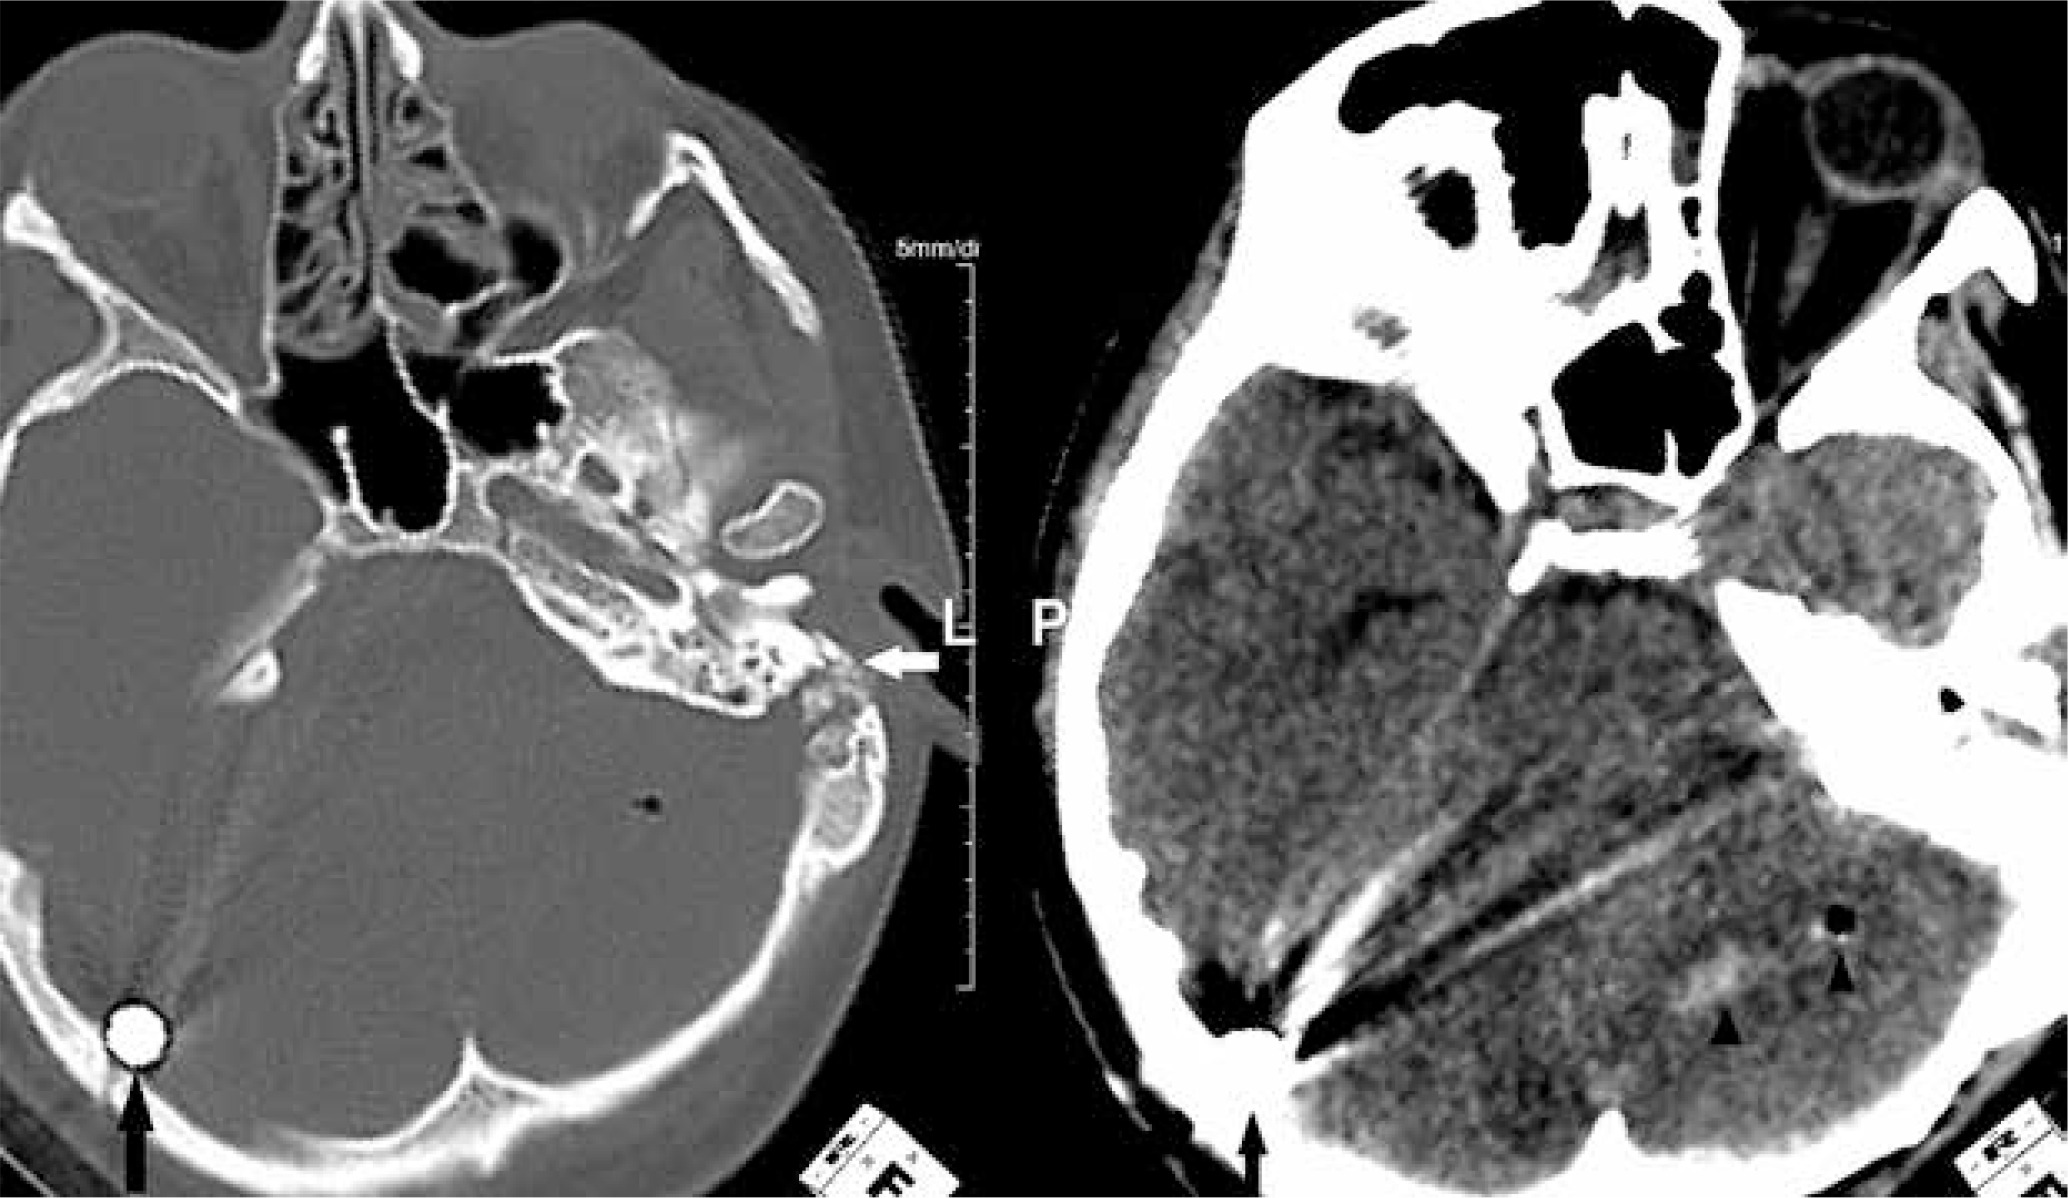

Seven primary-type tympanic membrane perforations were noted. Cerebral and cerebellar injuries were seen in four patients including subarachnoid haemorrhage and parenchymal haemorrhage, with three of them having intracranial ball bearing penetration (Figure 1). Three of the four patients had sustained intraocular injury from the ball bearings in the bomb, with two requiring a total vitrectomy, and the third patient died from life-threatening injuries (Figure 2). Maxillofacial, orbital, mastoid, skull base fractures were seen in six patients, and one had tertiary type orbital and maxillofacial fractures. Only one patient encountered cervical vertebra fracture. Subdural or epidural haematoma was not seen.

Figure 1

Non-contrast computed tomography of the head in the bone and parenchyma window. A ball bearing is seen adjacent to the internal tabula of the occipital bone (black arrows). Haemorrhage and air density are present in the left cerebellar hemisphere (arrowheads). The left temporal bone fracture indicates the entry of the ball bearing (white arrow)